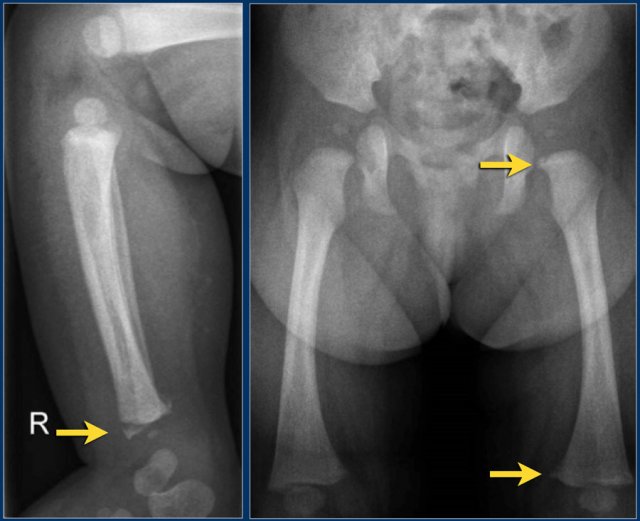

آزمایشات / تشخیص

پس از معاینه فیزیکی و بررسی تاریخچه پزشکی، ممکن است تعدادی آزمایش برای تشخیص عفونت های مشکوک لگن مورد نیاز باشد. اینها ممکن است شامل موارد زیر باشد:

آزمایش خون (برای تشخیص هر گونه عفونت منتقله از خون).

اشعه ایکس.

سی تی اسکن.

اسکن امآرآی.

اسکن استخوان.

بیوپسی بافت از استخوان.

تجزیه و تحلیل مایع مفصلی (برای تشخیص عفونت در مایع سینوویال اطراف مفصل).